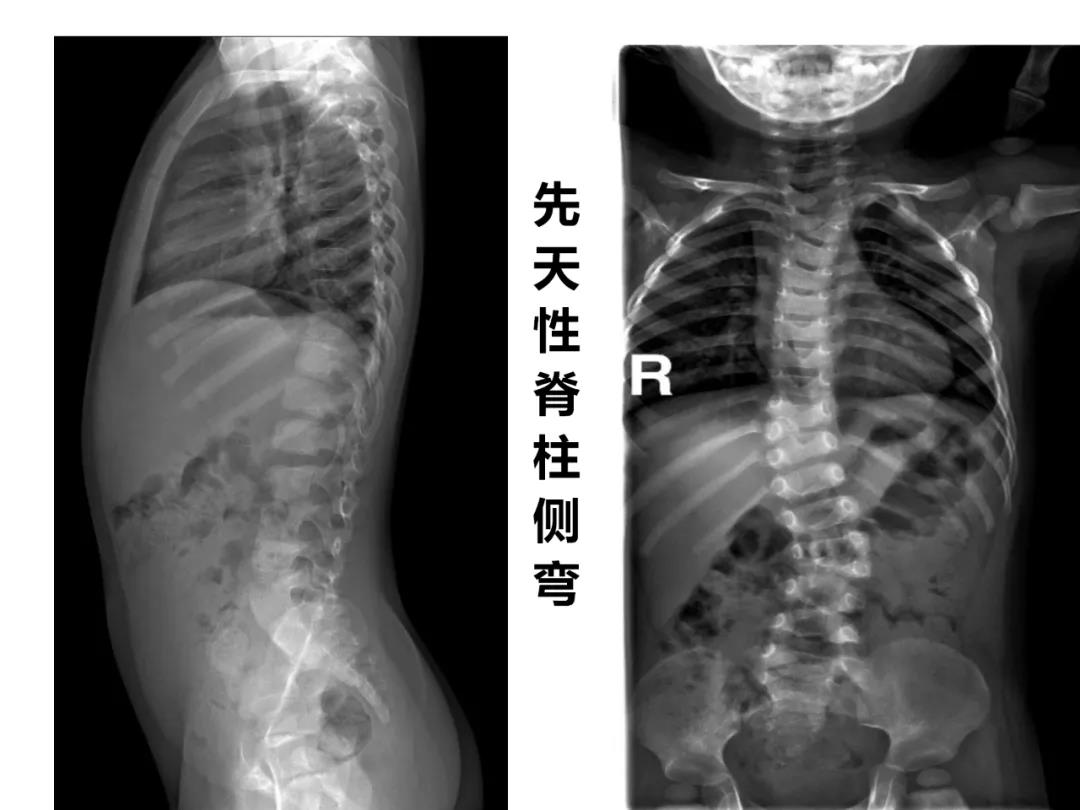

小儿骨科X线片汇总,临床读片宝典!